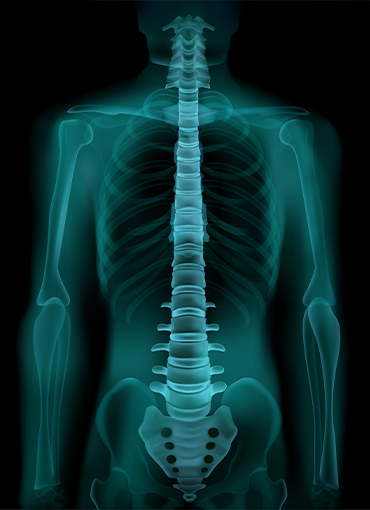

Biyoteknoloji hizmetlerimiz kapsamında; ortopedik ve cerrahi uygulamalarda kullanılan medikal ekipmanların tedariğini ve çözümlerini sunuyoruz. Klinik gereksinimlere uygun, kalite ve güvenlik standartları gözetilerek seçilen ürünlerimizle sağlık profesyonellerinin ihtiyaçlarına etkin çözümler sağlıyoruz. Ürün yelpazemiz, modern cerrahi süreçleri destekleyecek şekilde yapılandırılmıştır.

Artroskopik uygulamalara yönelik gelişmiş ekipman ve enstrüman çözümlerimiz hakkında detaylı bilgi almak için bizimle iletişime geçebilirsiniz.